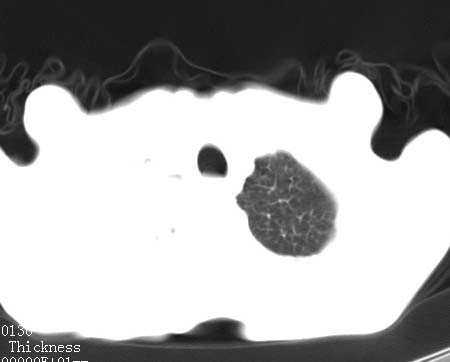

病人女 60岁 咳嗽 气促十余天,大叶性肺炎.

右肺上下叶均见 大片状密度增高影,边界清晰,其内可见支气管充气征,气管支气管通畅。纵膈略向右移位,其内无肿大淋巴结影。首先考虑炎性病变。不排除一些特异性的炎症。不知道发烧吗??wbc高吗??建议治疗后复查!!

看影响还是首先考虑炎性改变,建议实验室检查,还有要警惕炎性肺泡癌,具有的枯枝征象。

右肺感染性病变(大叶性肺炎可能);建议抗炎治疗后复查。

看影像还是首先考虑炎性改变,建议实验室检查,还有要警惕炎性肺泡癌,具有的枯枝征象